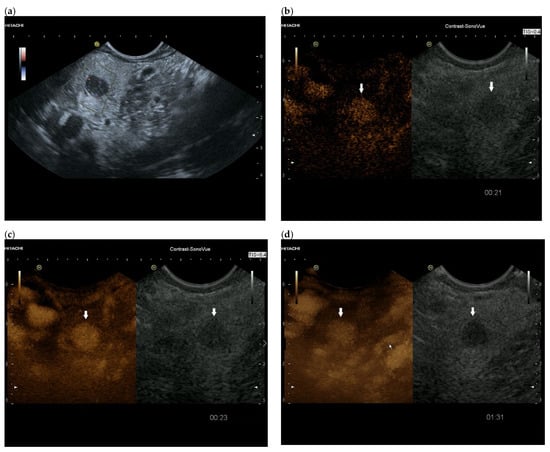

3.4. CEUS and CH-EUS

| Colour Doppler Imaging | RCC metastases are hypervascularized Most other pancreatic metastases are hypovascularized | No hypervascularization | Hypervascularized |

| Cases | CEUS | CH-EUS | ||

|---|---|---|---|---|

| Arterial Phase | Venous Phase | Arterial Phase | Venous Phase | |

| RCC metastases [83] (n = 4) | Hyperenhancement, Early | Hyperenhancement | ||

| RCC metastases [61] (n = 3) | Hyperenhancement, homogeneous pattern | Slow washout | ||

| RCC metastasis [86] (n = 1) | Hyperenhancement, Inhomogeneous pattern | No washout | ||

| Melanoma metastasis [63] (n = 1) | Iso- to slightly hypoenhanced | Hypoenhanced | ||

| Melanoma metastasis [87] (n = 1) | Isoenhanced | Hypoenhancement of the peripheral rim, central non-enhancement | ||

| Melanoma metastasis [61] (n = 1) | Isoenhanced, heterogeneous | Fast washout | ||

| SCLC metastasis [83] (n = 1) | Hyperenhancement | Rapid washout | ||

| Breast, ovarian, colon metastases, sarcoma metastases [61] (n = 6) | Hypoenhancement, homogeneous or heterogeneous | Fast or slow washout | ||

| Lymphoma metastasis [61] (n = 1) | Hyperenhancement, homogeneous pattern | Fast washout |